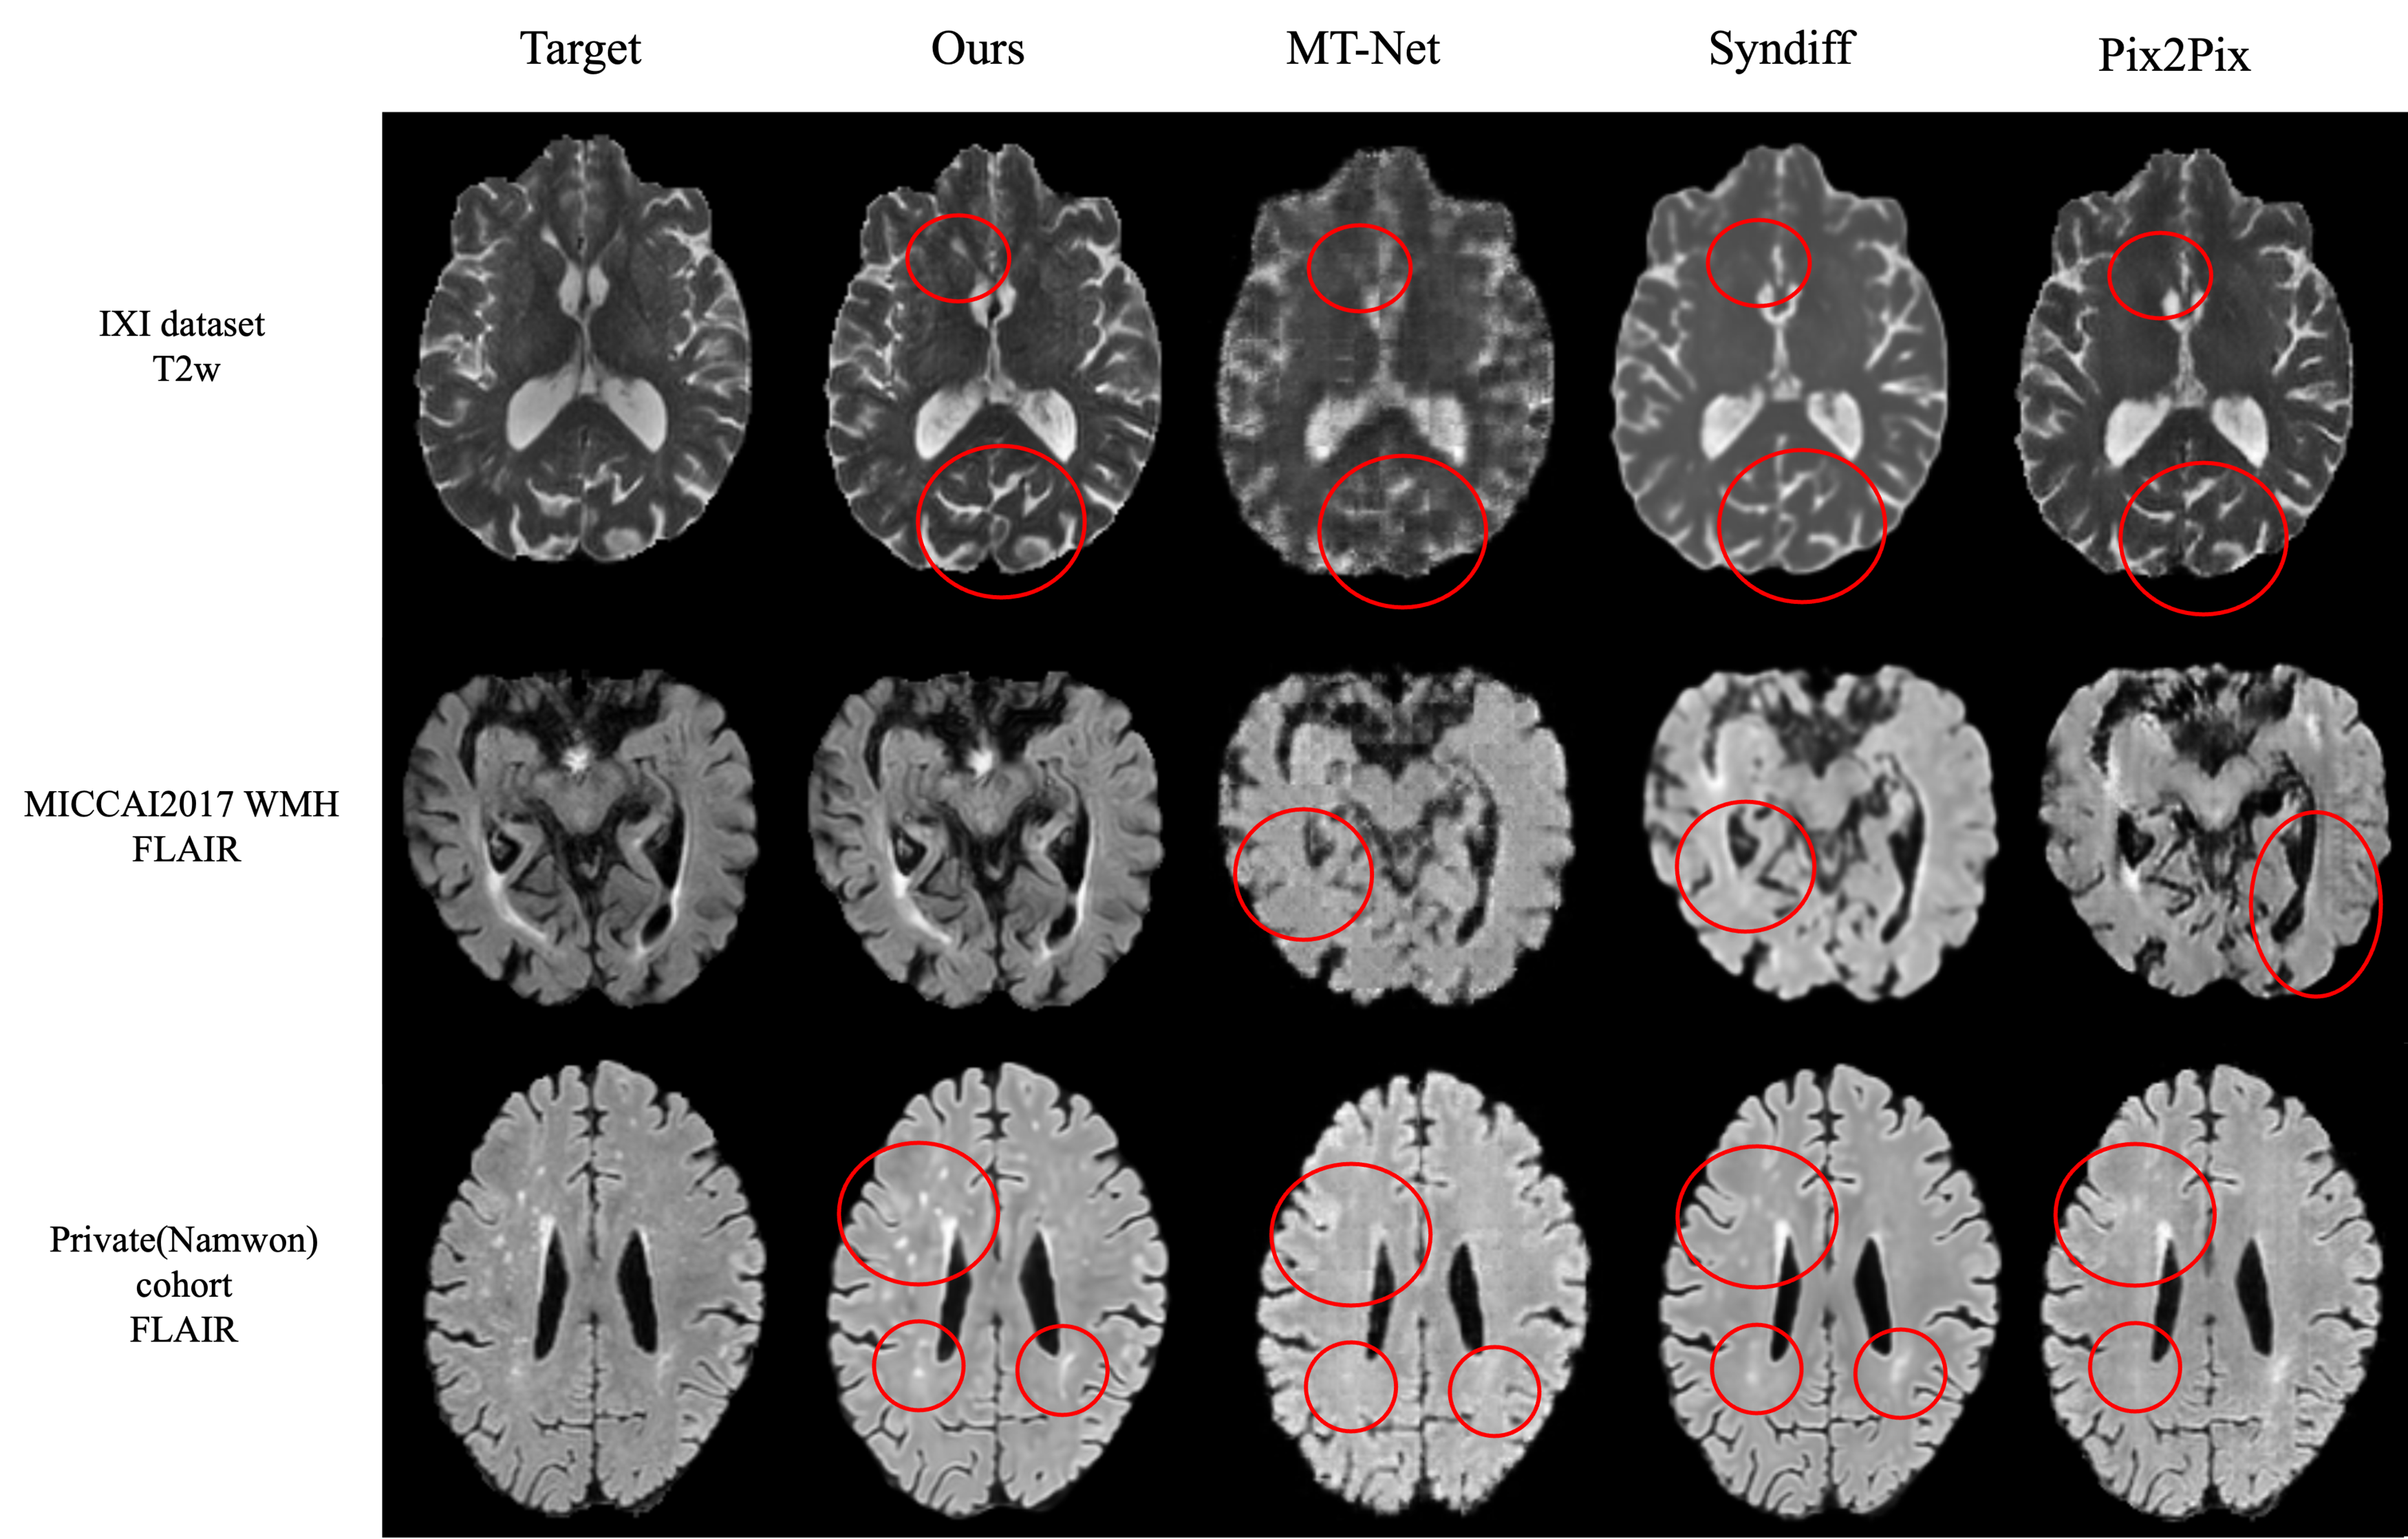

5.1 Brain MR Image synthesis result

All experiments used T1w as the source modality, which serves as an optimal source sequence for synthesis due to its rapid acquisition time, clinical efficacy, and superior anatomical delineation [41]. The numbers in parentheses indicate the number of subjects used for training. For MT-Net, the format shows (pre-training subjects/fine-tuning subjects).

Our FGSB framework demonstrates exceptional data efficiency, achieving competitive or superior performance with dramatically fewer training subjects compared to existing methods(2, 3, 4, 5). Remarkably, FGSB trained on only 2-3 subjects consistently outperforms baseline methods trained on 10-25 subjects, while matching or exceeding state-of-the-art performance when using comparable training data. Our framework excels in preserving clinically essential structures, particularly lesions and white matter hyperintensities (WMHs), which are often lost or distorted by competing methods.